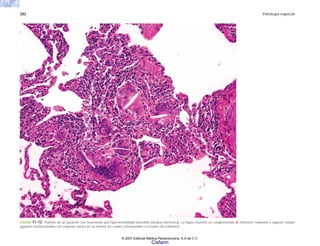

la fractura, de la herida o de los desgarros producidos

por la fiera, sino que en realidad todo el organismo